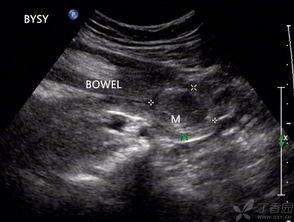

四、成人肠套叠的诊断

成人肠套叠的诊断主要依靠以下方法:

1. 影像学检查:如X光、CT、MRI等,可以清晰地显示肠套叠的情况。